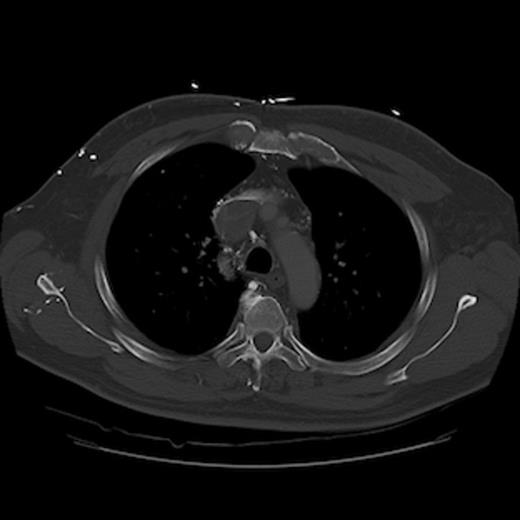

A 67-year old gentleman presented with progressive head and neck swelling and discomfort for several months. His symptoms were pronounced by bending over or straining in the bathroom. His symptoms worsened and he was referred for thoracic surgery consultation after a mass was seen on chest x-ray. He was diagnosed with SVC syndrome secondary to a mediastinal mass, demonstrated best by computed tomography (CT) [Figures 1, 2, 3].

CT of the chest (coronal section) with intravenous contrast: demonstrates large thrombus obstructing the superior vena cava down to the right atrium